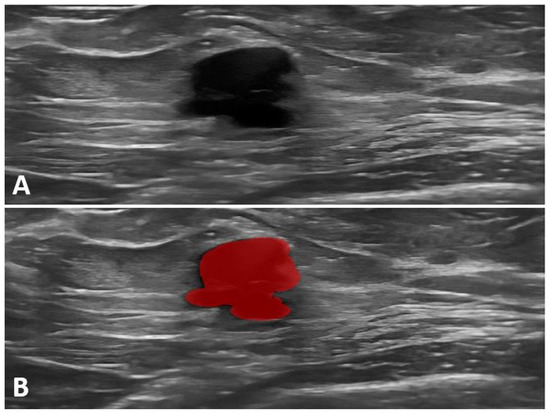

2.3. Ultrasound Imaging and Data Acquisition

2.6. Feature Selection, Statistical Analysis, and Model Development